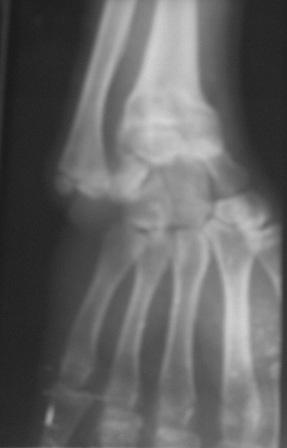

Доброго времени суток уважаемые коллеги! Обратился б-ной 16 лет.Травму получил 9-лет назад, перелом лучевой кости и надмышелковый перелом плеча. Имеется деформация л/з сустава типа лучевой косорукости, укорочение п/плечья, отсутствие локтевой девиации, cubitus vaus под углом 25 гр . Просит первоначально исправить деформацию л/з сустава и восстановить длину п/плечья. Наш план- остеотомия дистального метафиза лучевой кости, коррекция деформации и удлинение по методу Илизарова. Уважаемые коллеги, помогите советом! Можеть быть есть какие-то нюансы , или другие методы? Снимки прилагаются. С уважением Абдурашид.

С учетом возраста больного предлагаемая Вами тактика представляется оптимальной. Боковая ренгенограмма низкого качества, но кажется дистальный фрагментдостаточно короткий - надо постараться выполнить остеотомию точно на высоте деформации иначе трудно будет устранить угол.

Спасибо! Я видимо так и буду делать, но вот что смушает, ведь локтевая кость тоже укорочена на 3-3.5см, после удлинения лучевой кости дальше что делать, удлинить и локтевую кость? что-то в доступных литературах найти не могу!

Уважаемый Абдуращид, предложенный Вами план лечения адекватный и не вызывает сомнений.

Для полного представления о деформациях, желательно посмотреть рентгенограммы локтевого сустава.

И еще один момент, у пациента имеется укорочение всего сегмента, удлинение лучевой кости и коррекция угловой деформации не уровняет длину предплечья со здоровым. Это надо озвучивать и обсуждать с пациентом.

Под рукой оказалась минирентген локтевого сустава, где можно увидеть cubita valga(последствие надмышелкового перелома).

Уважаемый коллега, ваш план вполне логичен. Копенсация укорочения лучевой кости с коррекцией деформации. Устранения деформации только за счёт формирования клиновидного регенерата думаю будет недостаточно для компенсации укорочения. В связи с этим целесообразно монтировать аппарат с учётом формирования трапецевидного регенерата.

U bolnogo po vidimomu byl growth arrest of the distal radius.

Ya by ne nakladyval nikakih external, namnogo proche ukorotit distal ulna , fixation by plate , and corrective distal radius osteotomy(moghno zafixirovat KW ).6-8 weeks cast i vse dela.Ya za Ilizarova , no na kisti esli moghno bez nego vsegda luchshe.Predloghennaya techika ochen legk perenositsya (delal mnogo raz sam)